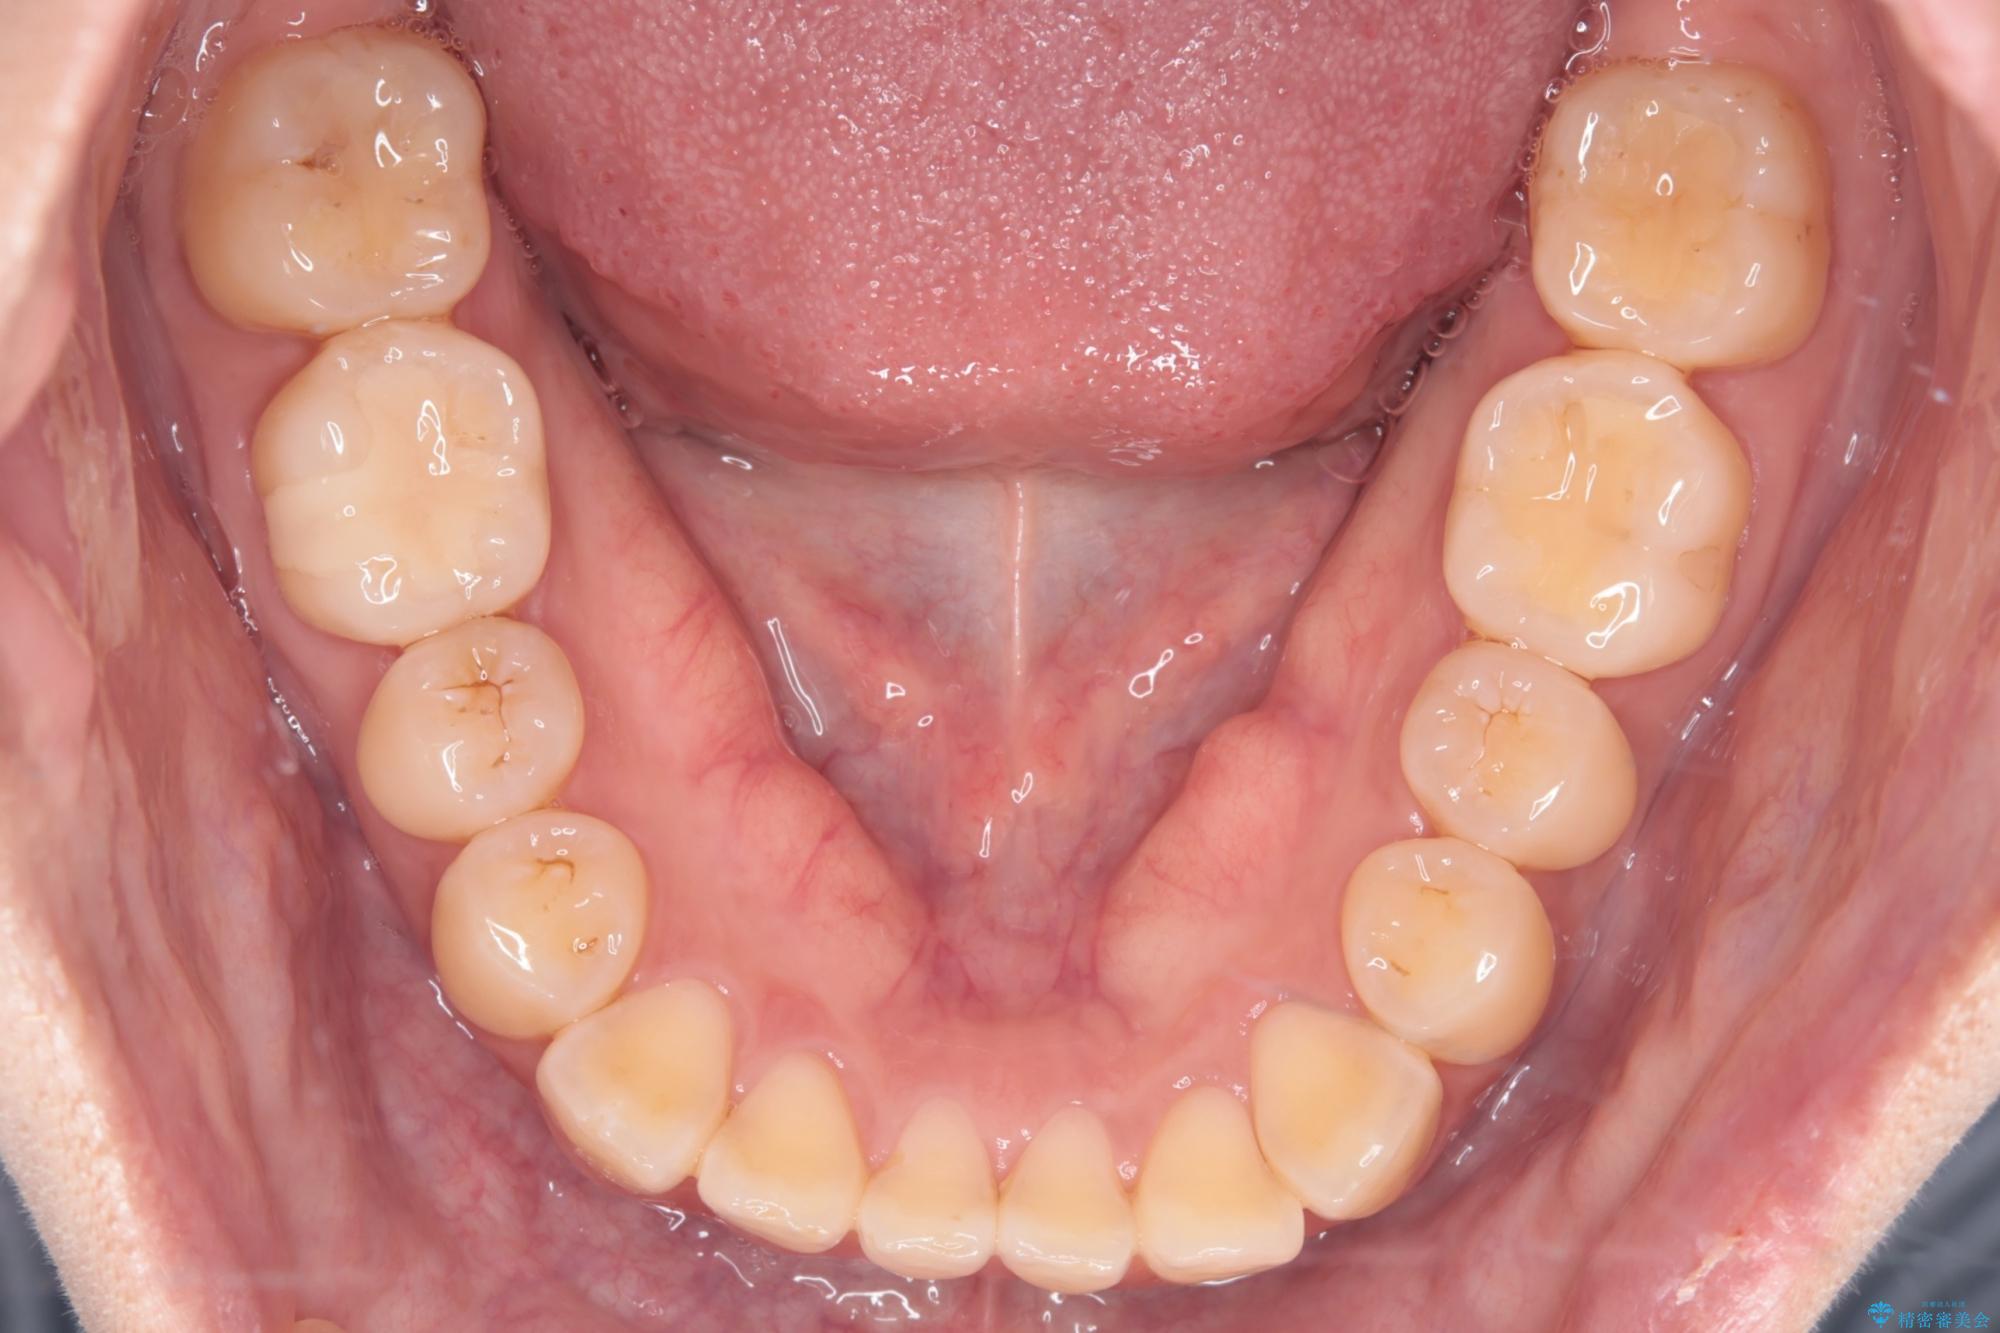

上の前歯のねじれが気になるとご来院された患者様です。

前歯の捻れとがたつきを改善するために、IPR(歯と歯の間を削る処置)と歯列拡大をすることで歯並びを整えていく治療計画を立てました。